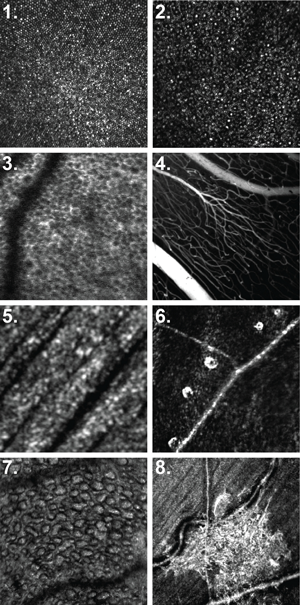

Commercial and custom-built AO devices are available in ophthalmology with significant differences between them including, in terms of ease of use, cost, maintenance, and the depth and breadth of their capabilities [2]. The custom devices use a superior optical design that nulls out the aberrations of the imaging system. The result is a diffraction-limited system, with consequent higher resolution. Many of the parts are custom optics, so they are more expensive, but give better performance. The highest resolution devices to date are custom-built Adaptive Optics Scanning Laser Ophthalmoscopes (AOSLOs), which are able to exquisitely visualise retinal anatomy including microvasculature, including cellular blood flow, cone, rod and retinal pigment epithelium mosaics, and the retinal nerve fibre layer [2-5] (Figure 2).

Figure 2: In vivo images acquired with Adaptive Optics Scanning Laser Ophthalmoscope (AOSLO). 1) Macular cone photoreceptor mosaic. 2) Rod and cone photoreceptor mosaic. 3) Retinal pigmented epithelium mosaic. 4) Contrast aided angiography. 5) Retinal nerve fiber layer (RNFL) 6) Inner retinal blood vessels without contrast. 7) A cross-sectional view of micro-retinal cysts in a patient with retinitis pigmentosa. 8) Hyper-reflective area in the RNFL in a patient with glaucoma. These patches are not observable with conventional imaging and studies are ongoing with regard to their exact aetiology. Courtesy of Professors Carroll and Dubra.